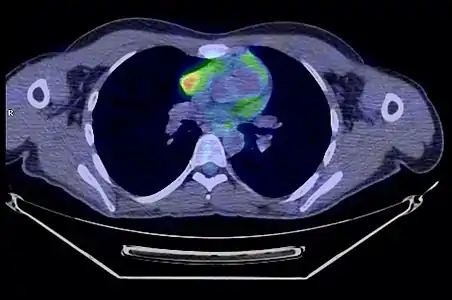

La place du TEP scanner dans le diagnostic des thymomes est encore débattue[31]. S'il existe bien une hyperfixation de la tumeur, son rôle dans le diagnostic de l'extension locorégionale reste à préciser[33].

- Thymome de type B1 en TEP scanner

Coupe transversale. Les trois clichés sont extraits du même examen.

Coupe transversale. Les trois clichés sont extraits du même examen. Coupe frontale ; la tumeur est à l'intersection des lignes rouges.

Coupe frontale ; la tumeur est à l'intersection des lignes rouges. Coupe sagittale ; la tumeur est à l'intersection des lignes rouges.

Coupe sagittale ; la tumeur est à l'intersection des lignes rouges.